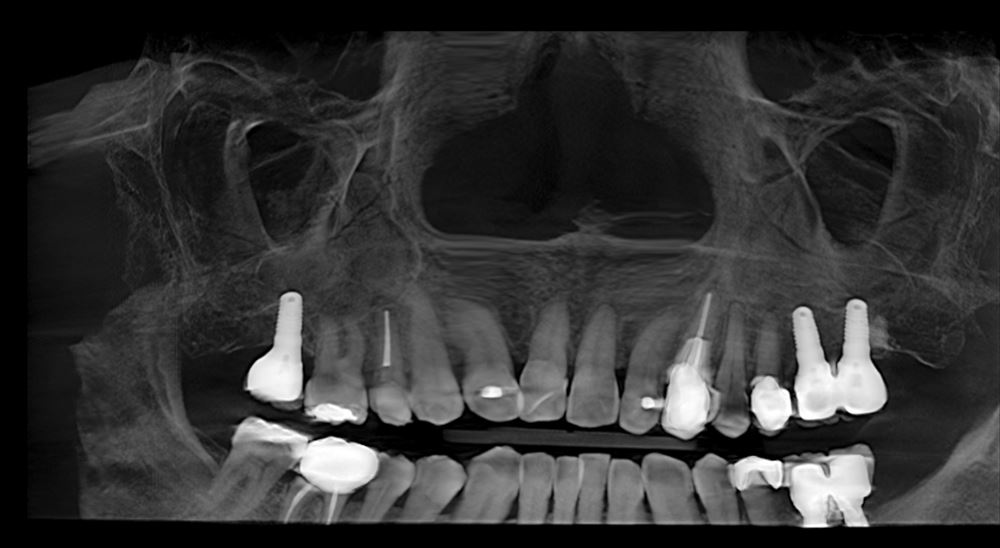

ちなみに下記のCTに写っているインプラントは私がすべて行った物です。下もあわせて5本。すでに下は9年経過です。まったく問題ありません。

歯が欠損していたときの第一選択はインプラントがやはり一番安定していると思います。ただ診断をしっかりして保存が可能であるという場合は今回の様に精密根管治療や精密歯周病治療で保存します。包括的に考える事が大切ですね!家族にお勧めしている治療です。